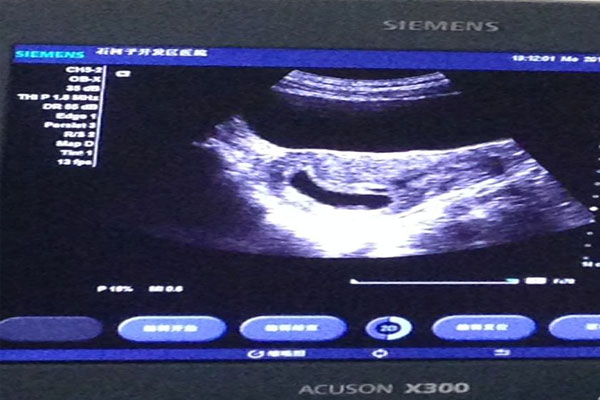

四:b超检查

在准确度上,以上这几种方法谁也赢不了B超,不过等待的时间也是最长的。如果大姨妈正常规律,在停经后的一个月左右,受孕成功的孕妈妈们就可以看见妊娠囊,就是B超单上那个闪闪的光环,最迟40天左右是可以看到胚芽和胎心的,当然这并不是绝对,胚芽要长到2mm大小才能看见原始胎心跳动。另外一般来讲,阴道B超比腹部B超能够提前3~7天看见妊娠囊。

B超检查时间:去医院做B超是诊断女性是否怀孕最正确可靠的方法。B超检测早孕的时间一般是在月经推迟一周左右的时候检查,此时可以去医院做B超检查看是否怀孕,如果在B超下能看到子宫内有圆形的光环又称妊娠光环就表明怀孕了。